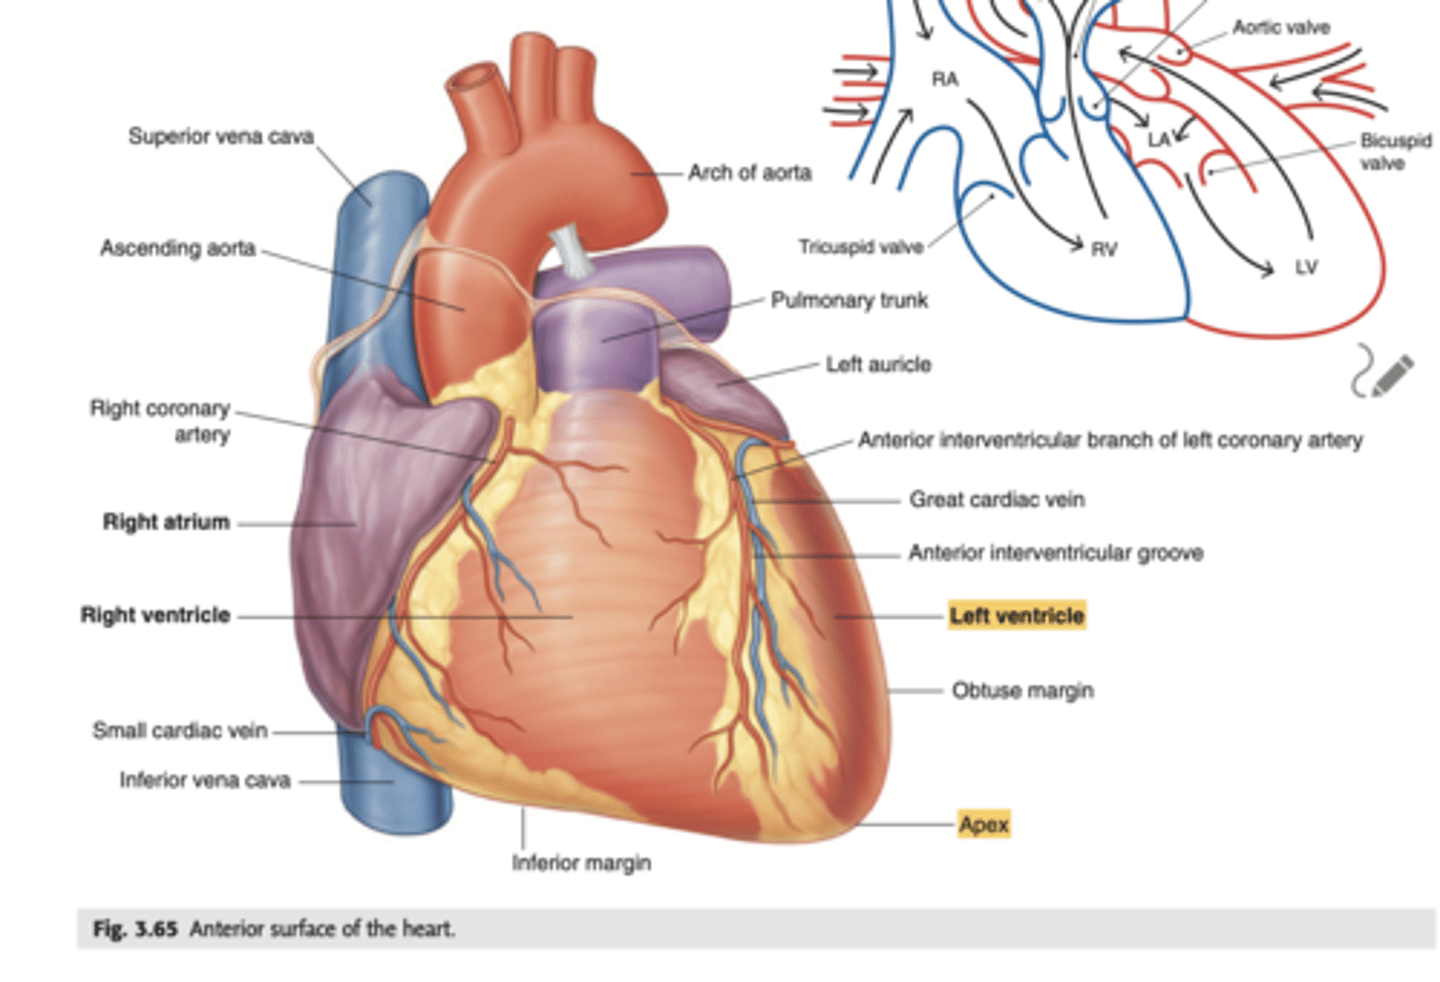

Describe the apex in the heart's anterior view

. Point to left side, downwards.

. At the level of the 5th intercostal space (we will auscultate the apex of the left ventricle)

Describe the Sternocostal Surface

Most of the anterior surface of the heart corresponds to the right ventricle.

What are the atrial appendages?

Rough trabeculated region of the atria (Extensions of the atria)

External portions of the atria, (Real cavities of the right and left atrium being posterior to these auricles)

ALSO CALLED AURICLES

Describe the location of the main arteries in the anterior view of the heart

The pulmonary trunk exits the right ventricle

. aorta exits the left ventricle.

During early heart development, the pulmonary artery is on the left and the aorta on the right because they develop from a common tube (truncus arteriosus).

What is the pulmonary trunk?

. major blood vessel that plays a crucial role in the circulatory system by carrying deoxygenated blood from the heart to the lungs.

. Divides into left and right pulmonary arteries